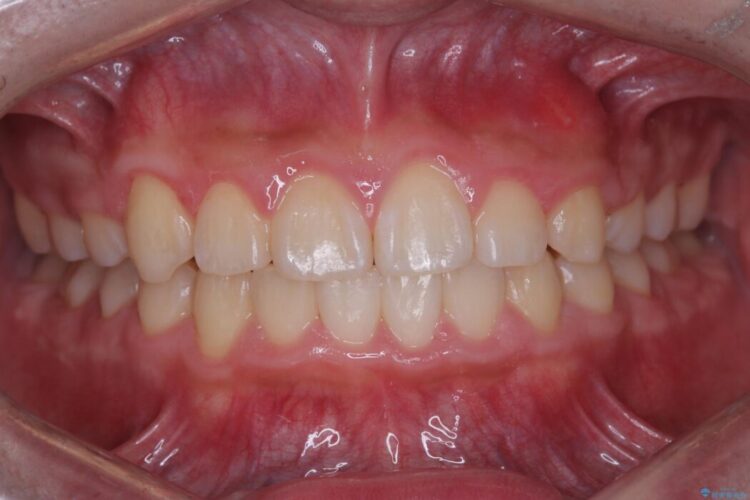

破折したセラミックインレーのやり替え

他院で装着されたセラミックインレー(MOD窩洞)が破折したとご来院されました。

治療期間(治療回数):1ヶ月(2~5回) | 概算治療費:15.4万円(税込)(オールセラミッククラウン14.3万円+仮歯1.1万円)